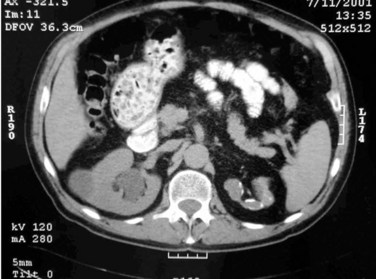

Plain radiographic findings in genitourinary tuberculosis may be seen in the GU tract, surrounding tissues, and up to 50% of patients may show positive findings on chest radiograph. Disparity in renal size on plain films may indicate early increase in size of the affected kidney due to caseous lesions or a shrunken fibrotic kidney of autonephrectomy. Calcifications are seen in 30% to 50% of cases (Roylance et al, 1970). Focal calcifications occur within the caseating lesions (Fig. 16–1). A characteristic diffuse, uniform, extensive parenchymal, putty-like calcification, forming a lobar cast of the kidney is seen with autonephrectomy (Muttarak et al, 2005). Calculi may also be seen in the collecting system or ureter secondary to stricture formation. Ureteral calcifications are rare and are characteristically intraluminal as opposed to the mural calcifications of schistosomiasis. Bladder wall calcifications are not very common except in late cases of bladder contraction. Calcifications of the prostate and seminal vesicles are seen in 10% of cases (Burrill et al, 2007).

Figure 16–1 Kidney-ureter-bladder radiographic view in a patient with left renal tuberculosis with associated calcifications.

Plain film findings suggestive of tuberculosis may be seen in surrounding tissues such as erosions of the vertebral bodies or calcifications in a cold abscess of the psoas muscle (Burrill et al, 2007).